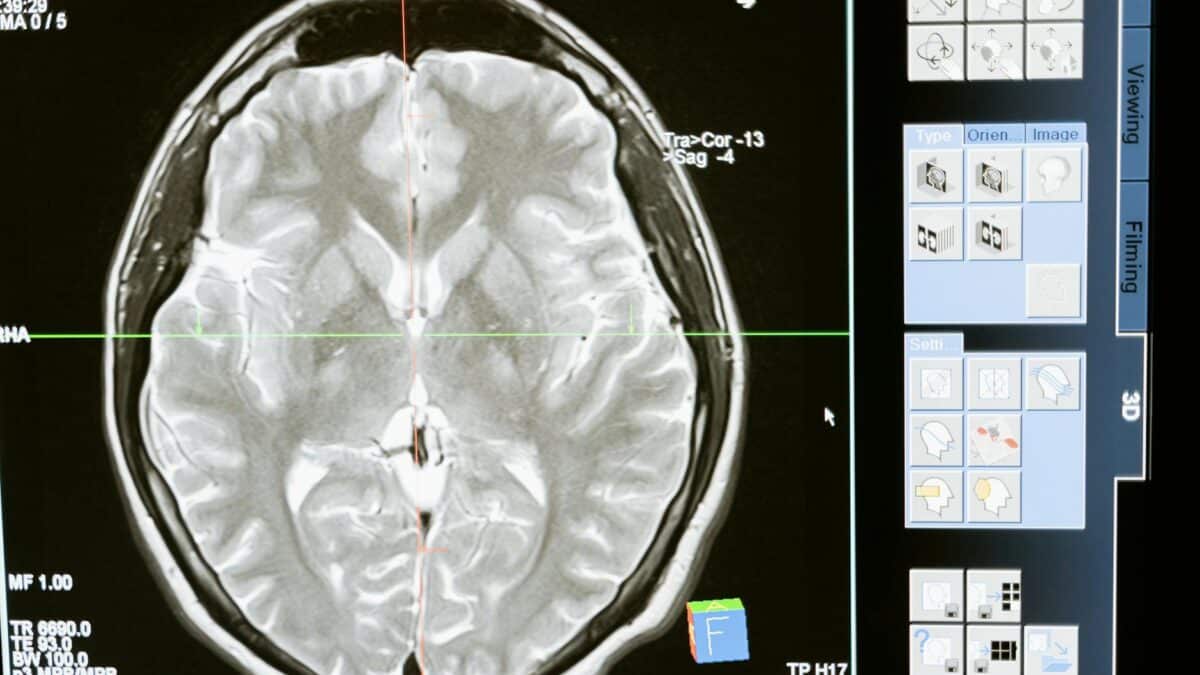

Echipele de cercetători internaționale au făcut progrese semnificative în înțelegerea mecanismelor neuronale implicate în percepția mișcării. Utilizând tehnici avansate de imagistică cerebrală, cum ar fi rezonanța magnetică funcțională, oamenii de știință pot acum observa în timp real activitatea neuronilor responsabili pentru detectarea mișcării.